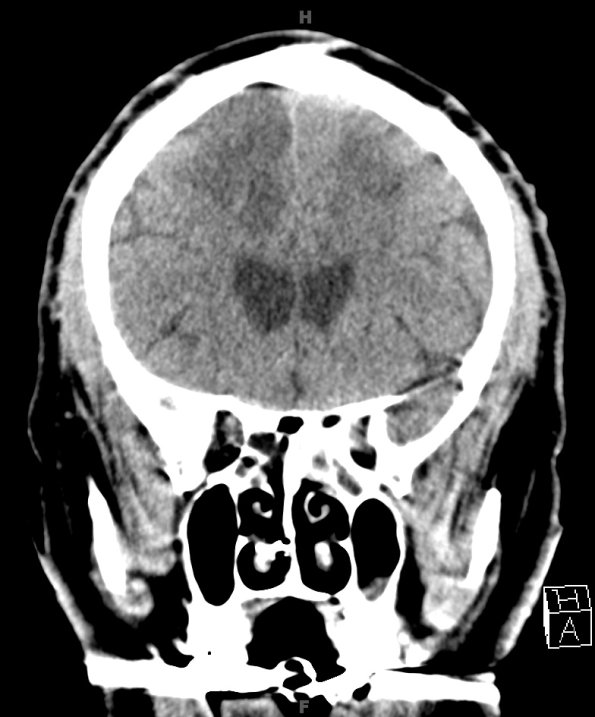

14A1,2 At autopsy the weight of the unfixed brain was 1390g. CT scans show bilateral hypodensities in watershed areas.